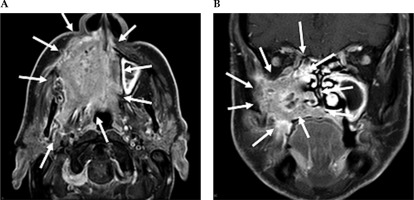

Fig. 2

Contrast-enhanced MRI neck scan demonstrating an extensively infiltrating necrotic malignancy centered in the right maxillary sinus, with heterogeneously bright contrast enhancement. A) Axial MRI imaging demonstrates a large avidly enhancing tumor centered in the right maxillary sinus. This extends anteriorly and laterally through the maxillary walls to the skin surface involving the right nasolabial fold and the facial muscles. Posteriorly, this extends into the pterygopalatine fossa, post-nasal space, and right masticator space infiltrating the right medial and latent pterygoid muscles. B) Coronal NIRI imaging demonstrates a large enhancing tumor centered in the right maxillary sinus, with non-enhancing areas of necrosis. This extends medially into the nasal cavity involving right middle and inferior nasal turbinate, along with infiltration of the right hard palate inferiorly